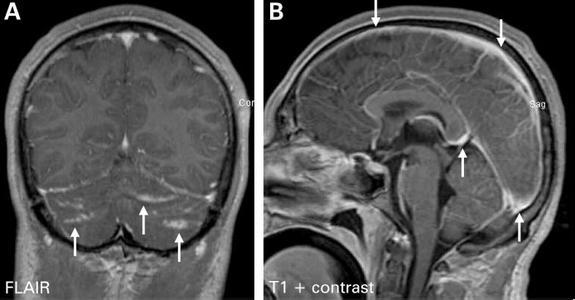

隐球菌感染的临床表现多种多样,可以包括从无症状、局限性肺部感染到播散性疾病。播散性疾病可以累及机体任何系统,最常侵犯中枢神经系统导致脑膜炎、脑膜脑炎及颅内局灶性肉芽肿。

脑膜脑炎的典型表现为严重头痛,可持续数周至数月,可伴随精神状态改变、人格改变、发热、昏睡及昏迷;其他神经系统并发症包括脑积水(交通性或非交通性)、视乳头水肿、突发感音性聋、颅神经麻痹、运动感觉障碍、小脑功能障碍和癫痫等。

图片引用自丁香园